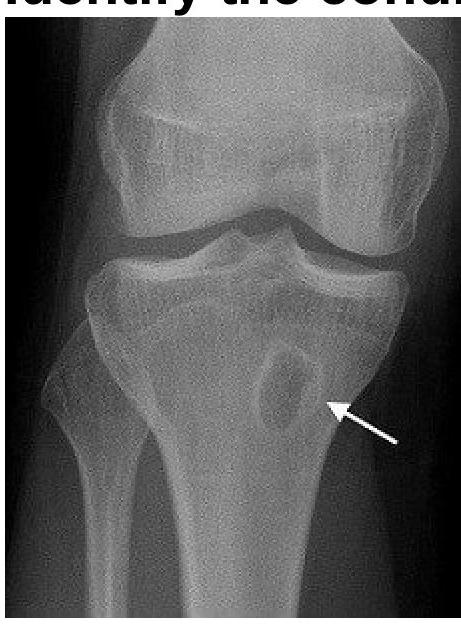

A 25-year-old male presents with localized pain in the tibia and swelling. Imaging reveals a bone abscess. Identify the condition.